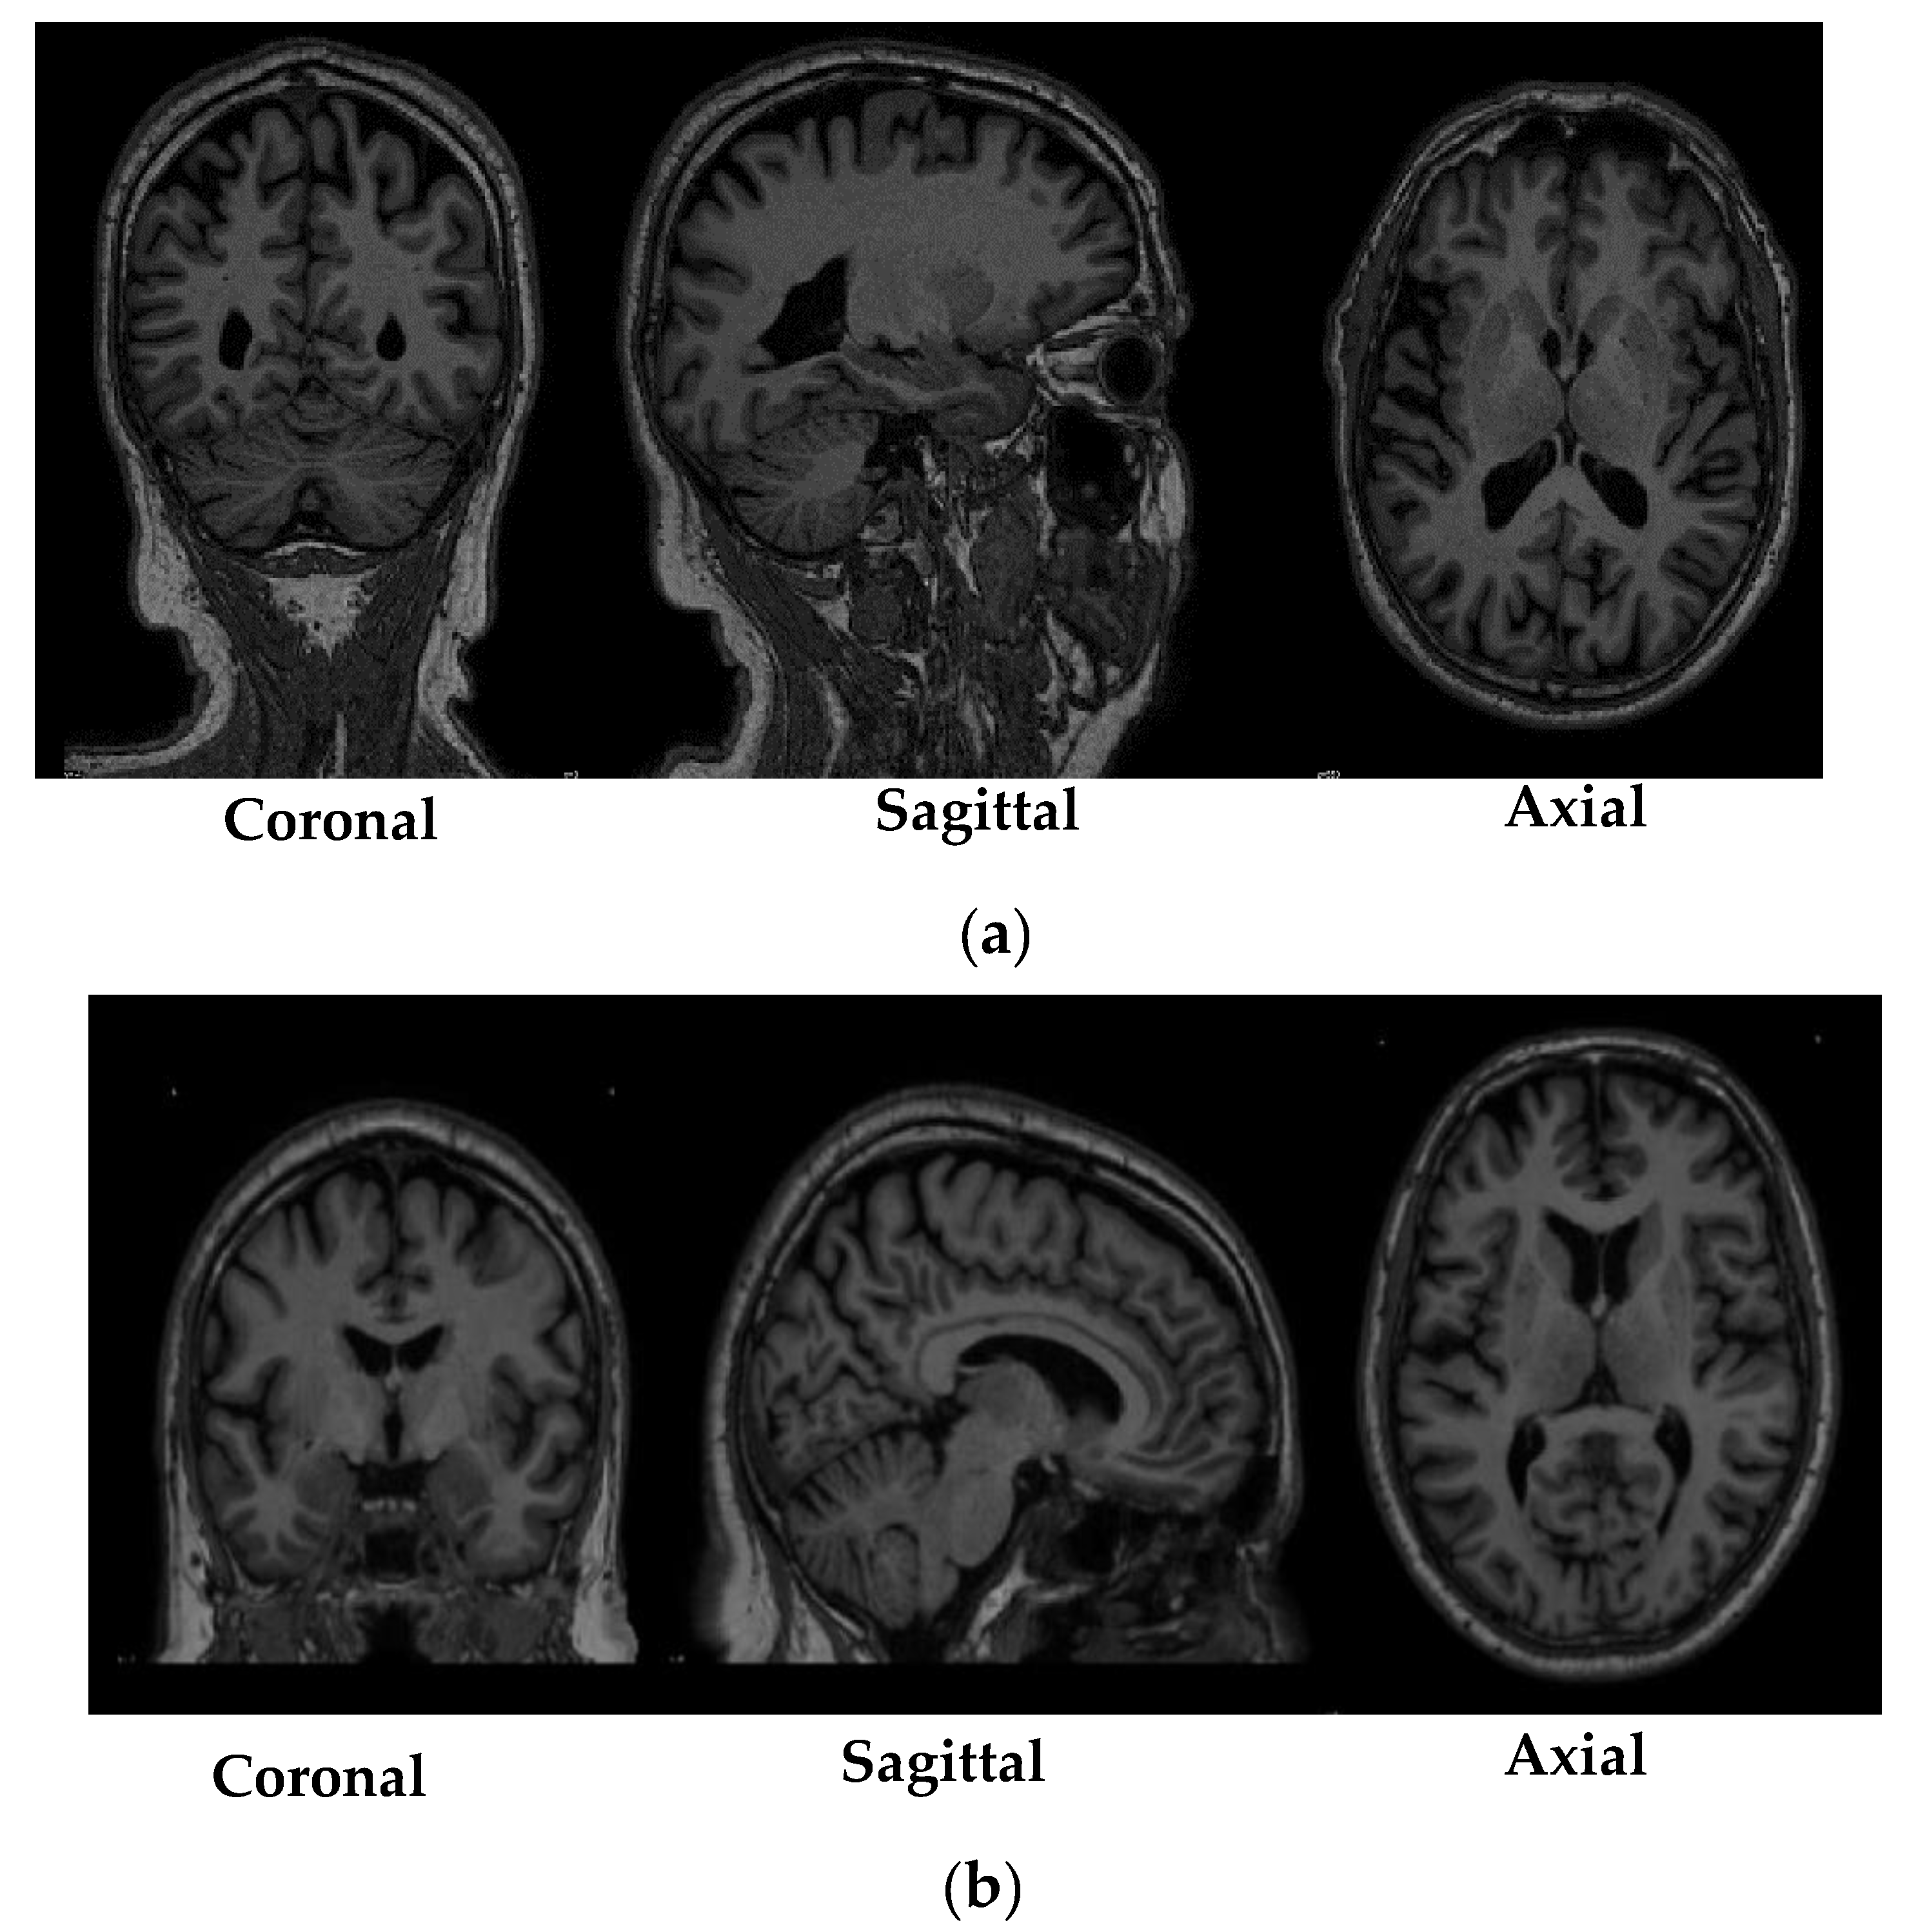

Table 3 shows the specifications of the scans that were obtained from the PPMI database. While Figure 1 depicted shows the sample of MRI scans belonging to both the research groups that were obtained from the PPMI database.

Figure 1.

Sample of Magnetic Resonance Imaging (MRI) scans obtained from the Parkinson’s Progression Markers Initiative (PPMI) database (a) MRI scan of a subject from the control group; (b) MRI scan of a subject from to the Parkinson’s Disease group.